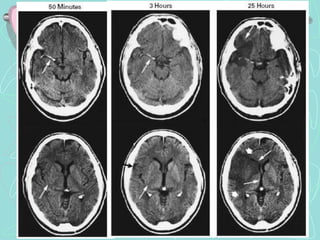

TOMOGRAFÍA COMPUTARIZADA DE ENCÉFALO

•Examen de elección en el Ictus agudo

ICTUS ISQUEMICO

•Aguda : lesión hipodensa.

•Subaguda (2º semana) Hipodensidad se intensifica

La detección precoz de imágenes hipodensas (menor

a 24 h) tienen pronóstico ominoso,

SIGNOS PRECOCES DE ICTUS ISQUÉMICO AGUDO

•1. Hipoatenuación de cinta insular

•2. Oscurecimiento del núcleo lenticular

•3. Hipodensidad / borramiento cortical

•4. Hiperdensidad de la ACM

TC Encéfalo, Infarto cerebral, territorio A. Cerebral Media Izquierda

SIGNOS PRECOCES DE ICTUS ISQUÉMICO

01. Hipodensidad de la corteza insular con disminución

de la densidad de la sustancia gris

02. Disminución de la densidad del núcleo lenticular

derecha. Infarto en putamen y brazo posterior de la

cápsula interna

03. Disminución de la densidad de la sustancia gris

cortical

04. Hiperdensidad del coágulo M1 de la ACM

Infarto masivo de la ACM